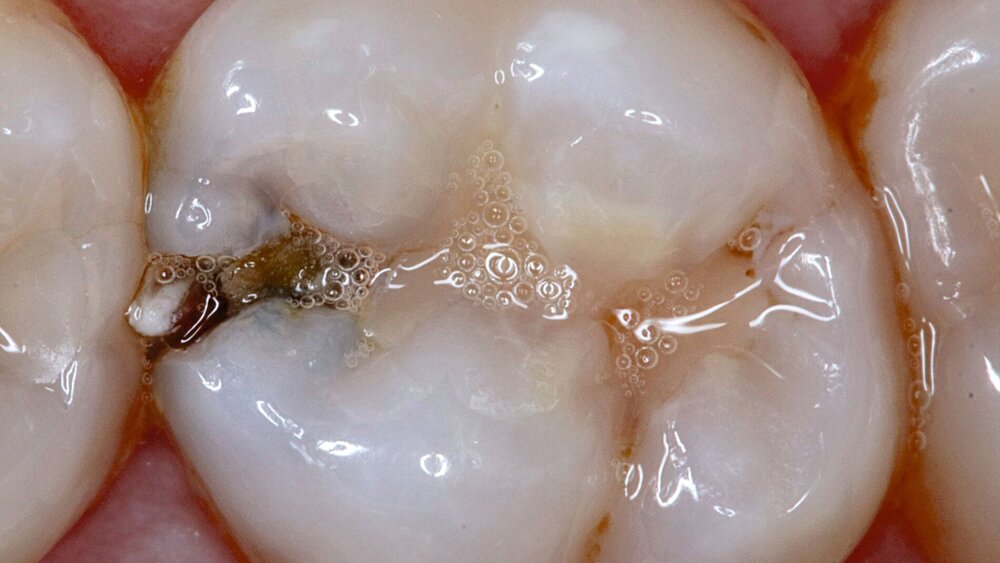

Die pulpanahe Karies im Praxisalltag

Sicherlich haben Sie schon öfter ähnliche Situationen erlebt: Der Patient stellt sich mit leichten Zahnschmerzen vor und nach der Befunderhebung stellen Sie kariöse Läsionen fest, die sich radiologisch als pulpanah erweisen. Es braucht vermutlich gar nicht viel Erfahrung, um abzusehen, dass die vollständige Kariesentfernung nach klassischen Kriterien hier zu einer Pulpaeröffnung führen würde. Das Ziel ist klar: Die Pulpa soll vital bleiben. Doch welcher Weg ist heute der richtige?